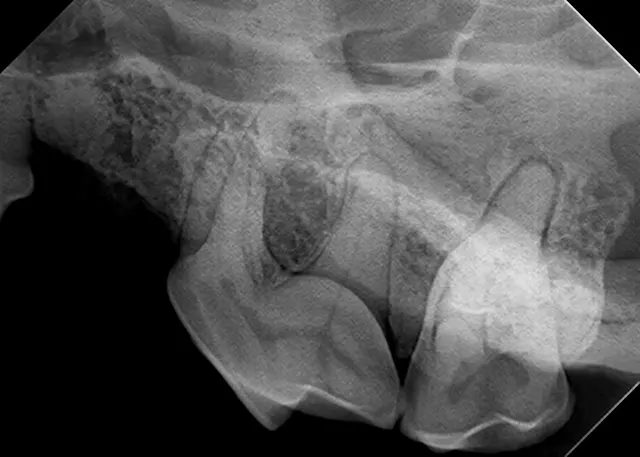

The relatively simple parallel technique is used to image the mandibular caudal cheek teeth on small dogs and cats.

For large dogs, use this technique to image teeth from the third premolar to the last molar. This portion of the oral cavity has room enough to place the sensor parallel and adjacent to the desired teeth, on the lingual aspect of the mandible. Then, aim the tube head perpendicular to the sensor.

This technique, which is used to image the rostral mandible and entire maxilla, is the only technique that produces an image without distortion when done correctly. Some technicians find the bisecting angle technique difficult to grasp; however, it can be simplified with proper patient and equipment positioning.

For example, image the caudal cheek teeth in the maxilla with the tube head at a 60° angle from the horizon.2 When the patient is positioned with the maxilla parallel to the horizon, the sensor can also be placed parallel to the horizon (ie, inside the oral cavity and adjacent to the desired teeth), making it much easier to visualize the angle.

Place the sensor horizontally inside the oral cavity, with the cusp tip of the desired teeth at the edge of the sensor. Placing the sensor inside the oral cavity will provide enough room to catch the radiograph image.

Radiographs should be taken in the same order each time. Starting with the right maxillary molars, move the sensor and tube head around the entire arch until the left caudal maxilla is reached. Then, position the patient in ventral recumbency and repeat the process, starting with the left mandibular molars. Continue around the arch until the right caudal mandible is reached. This sequence is suggested because full-mouth-series templates included in most digital software programs are arranged in this order and will result in the mirror image for correct viewing of radiographs.